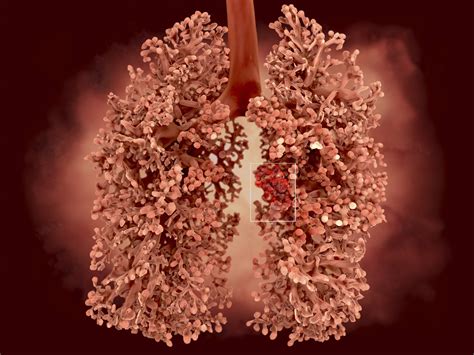

Popcorn Lung Picture

Popcorn lung, also known as bronchiolitis obliterans, is a rare and serious lung condition that has gained attention due to its association with the inhalation of diacetyl, a chemical used to give popcorn and other foods a buttery flavor. Understanding the causes, symptoms, diagnosis, and treatment of popcorn lung is crucial for those who may be at risk. This condition has garnered significant interest, particularly with the rise of vaping and the use of flavored e-liquids, which often contain diacetyl. A Popcorn Lung Picture can be a stark reminder of the potential dangers lurking in seemingly innocuous substances.

Popcorn lung is a type of obstructive lung disease that affects the smallest airways in the lungs, known as bronchioles. When these airways become inflamed and scarred, they can narrow or close, making it difficult to breathe. The condition is called "popcorn lung" because it was first identified in workers at a microwave popcorn factory who were exposed to high levels of diacetyl. Diacetyl is a flavoring agent that gives foods a buttery taste and is commonly used in the production of popcorn, baked goods, and other snacks.